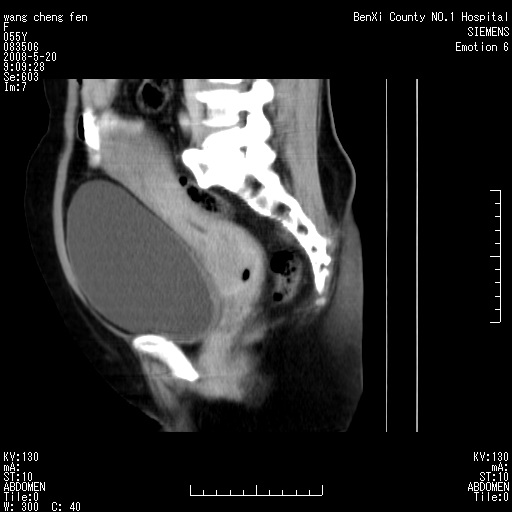

左侧附件区巨大囊实性病灶,边缘光整,病灶囊壁较厚,增强示囊壁及实性部分明显强化,强化呈度与宫体实质大致相同,宫腔积液征像,未见盆腔积液等其他异常,考虑左侧卵巢囊腺癌,不除外囊腺瘤及浆膜下肌瘤坏死

左侧附件区巨大囊实性病灶,边缘光整,病灶囊壁较厚,增强示囊壁及实性部分明显强化,强化呈度与宫体实质大致相同,宫腔积液征像,未见盆腔积液等其他异常。绝经后阴道流血3个月,结合病史左侧卵巢囊腺癌首先考虑,宫腔扩大不除外累及。期待结果。

支持浆膜下子宫肌瘤.之前由于网络原因未看全图片,现在重看,宫颈见一类圆形低密度影,增强轻度强化,低于肌层强化,宫腔扩大,考虑宫颈癌伴宫腔积液可能性大.

考虑巨大的浆膜下子宫肌瘤并变性坏死,宫颈周围静脉曲张。

囊实性肿块分隔厚度较大,厚薄不均,增强实性成分明显强化,有不规则阴道流血,卵巢囊腺癌可能性大。